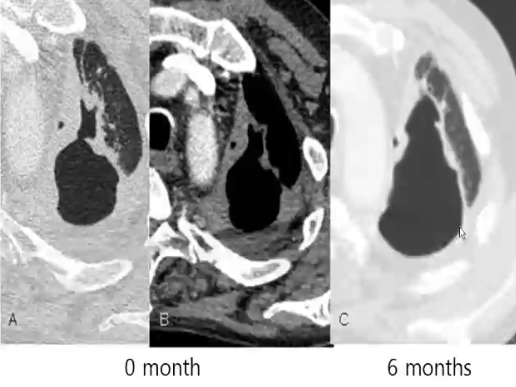

CT评价慢性肺曲霉菌病治疗后反应

❖ 与临床改善相关的CT评价指标

√真菌球消失

√空洞壁变薄

√病变邻近增厚胸膜变薄

√注意:单纯空洞大小变化与临床改善关系不大(空洞周围肺纤维化可造成结构扭曲、牵拉性支气管扩张等)